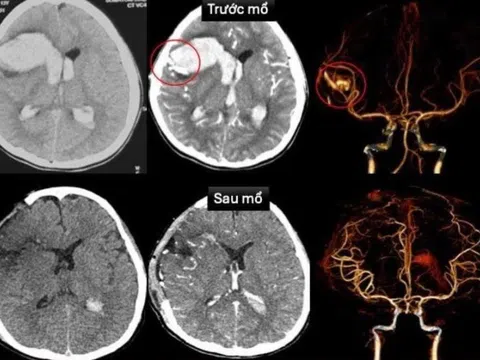

Bé gái TP.HCM vỡ mạch máu não, sốc tim nguy kịch khi đang ngủ

06:00 06/11/2025

Bé gái 13 tuổi rơi vào hôn mê sâu, sốc tim nguy kịch. Kết quả kiểm tra khiến bác sĩ bất ngờ khi em...